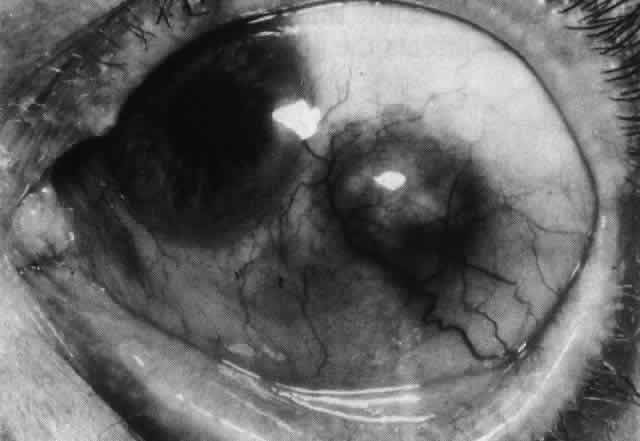

Necrotizing anterior scleritis without adjacent inflammation appears to be a well-defined condition with little relation in clinical features to necrotizing scleral disease, even though the pathology is similar and the final result is the same. Scleromalacia perforans is characterized by the almost total lack of any symptoms. It occurs almost exclusively in patients with long-standing polyarticular rheumatoid arthritis, the majority of whom are female (Figs. 49 and 50; Color Plate 1E).

Fig. 49. A white necrotic plaque developing in an area of sclera with practically no surrounding inflammation in a 60-year-old woman who had had Crohn's disease for 17 years.

Fig. 50. Scleromalacia perforans after treatment. The very thin sclera is covered by conjunctiva only and a few remaining large blood vessels. (Courtesy of Mr. HE Hobbs)

The anterior sclera loses its covering of episclera and develops an area of yellow-white necrotic slough over many months; this eventually separates or is absorbed, leaving the underlying choroid covered by either conjunctiva or nothing at all. As with necrotizing disease, the choroid does not bulge into this ectatic area; but unlike necrotizing disease, spontaneous healing of even small perforations is very limited once the necrotic tissue has been removed (see Fig. 50).

Fluorescein angiography is not helpful, except to indicate areas of vascular closure in an otherwise extremely thin, atrophic episcleral tissue.4 The formation of a sequestrum appears to be caused by arteriolar closure as opposed to the venular disease seen in the other forms of necrotizing scleritis.